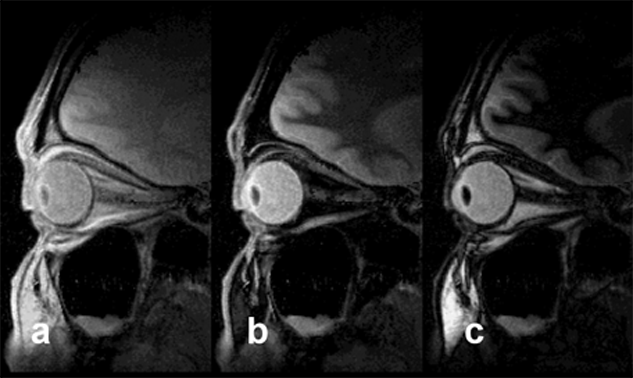

Figura 10-10:

STIR. In all images, TR = 4000 ms, TE = 10 ms; (a) TI = 50 ms, (b) TI = 240 ms, (c) TI = 450 ms. The fat­ty tissue close to the optic nerve disappears with a TI of ap­pro­xi­ma­te­ly 240 ms. Signal suppression is based on T1 relaxation times and not tissue specific. STIR should be used before in­ject­ing con­trast agents.

Signal suppression by STIR pulse sequences is based on T1 relaxation times; there­fore it is not tissue specific. This is the reason why STIR sequences should be used before the administration of contrast agents that facilitate T1 shortening [⇒ Krin­sky 1996].